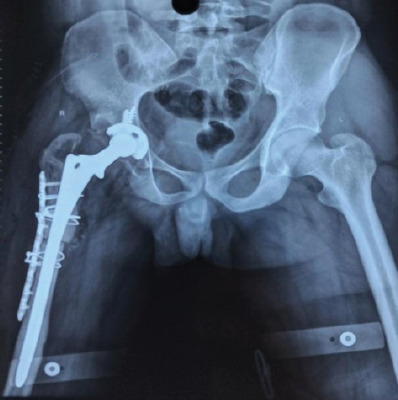

Case report: Here, we discuss the case of a 27-year-old male who had congenital hip dislocation, which was managed conservatively. At 18 years of age, he underwent a pelvic osteotomy and limb lengthening procedure. The symptoms subsided, but there was a recurrence of pain for the past 2 years, which was aggravated with movements. He was diagnosed with Crowe type IV dysplastic hip, and a right total hip with long stem was carried out along with subtrochanteric osteotomy. However, at 3 months of follow-up, the union was not sufficiently appreciated on radiograph, and the patient still complained of pain.

Conclusion: Hence, a single dose of BMAC injection was given, followed by three doses of PRP injections. The final follow-up was done 1 year after the surgery, and the patient had satisfactory outcomes.